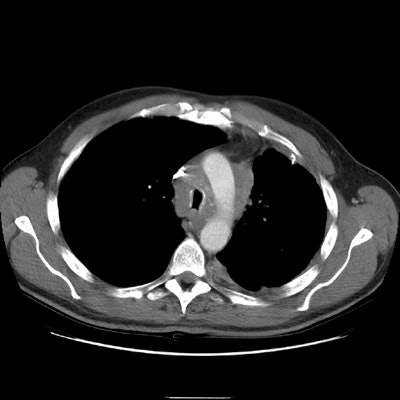

CT reveals an infiltrative mediastinal soft tissue abnormality encasing and narrowing the trachea.

The right upper lobe pulmonary vein can be seen just lateral and slightly posterior to the SVC. It is markedly narrowed and distorted by the mediastinal infiltrative soft tissue abnormality. No left upper lobe pulmonary vein is identified. The left pulmonary artery structures are narrowed and irregular.